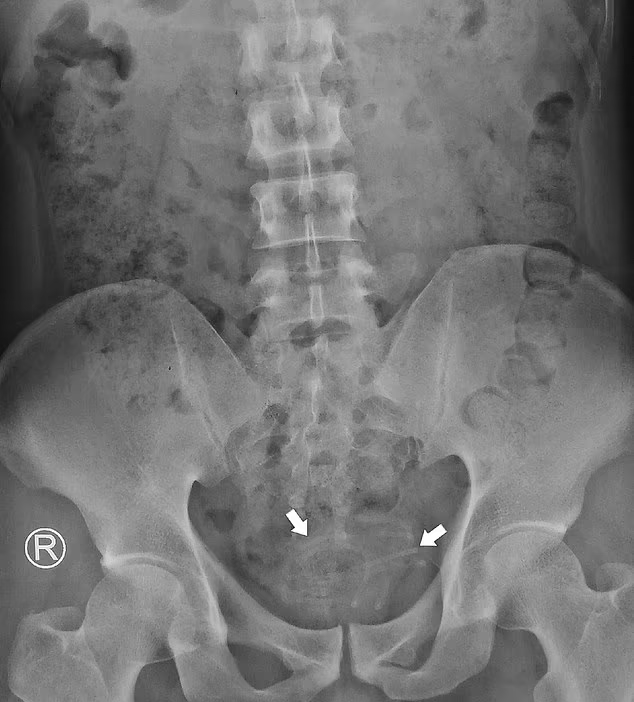

Doctors wrote in the journal Radiology Case Reports that the wire was ‘lodged in the bladder.’

The wire, which was 30inch long and 3mm wide, was coiled but, luckily for the man, had not attached to his bladder wall.